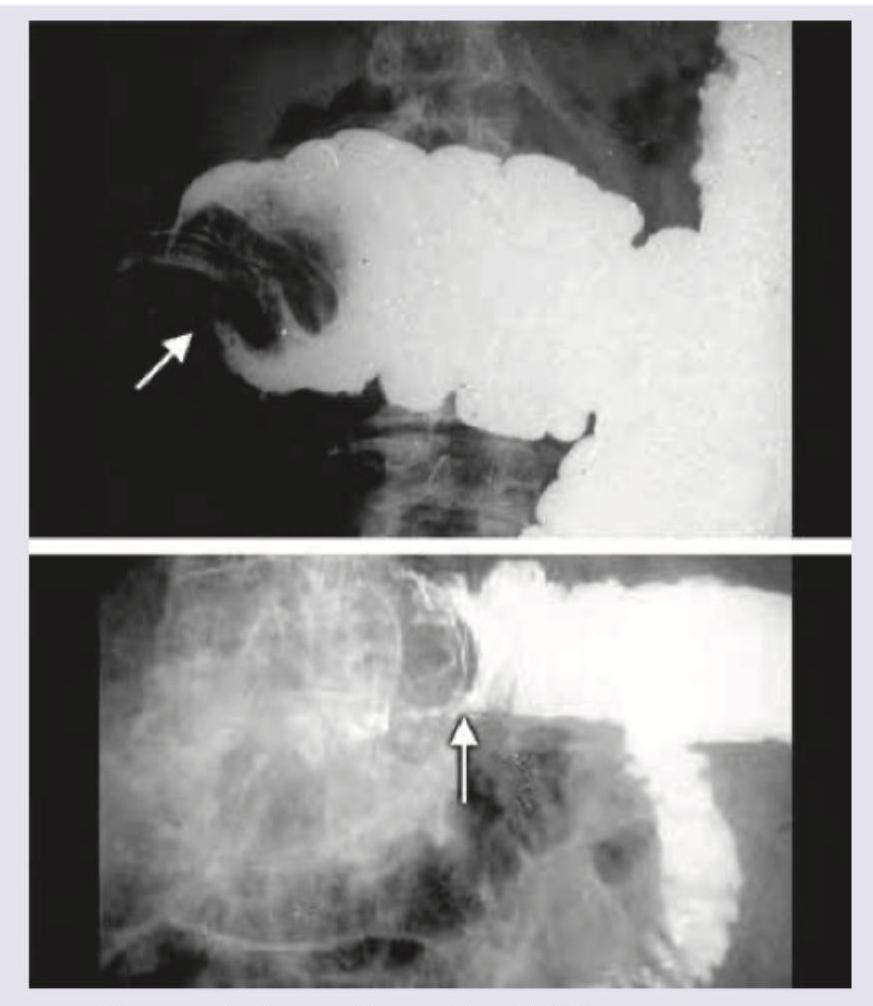

A baby presents with colicky abdominal pain. Mother gives a history of bloody stools. All the statements regarding this condition are true except:

Explanation: ***Rate of re-occurrence is $50 \%$ after non-operative reduction*** - The recurrence rate of intussusception after successful non-operative reduction (e.g., pneumatic or hydrostatic enema) is typically quoted as **5-15%**, not 50%. - A 50% recurrence rate would be unusually high and is not supported by standard clinical data. *Diagnosis is confirmed by USG* - **Ultrasound (USG)** is the preferred initial imaging modality for suspected intussusception due to its high sensitivity and specificity. - The classic "**target sign**" or "**donut sign**" on ultrasound confirms the diagnosis. *Seventy percent of the cases can be reduced nonoperatively* - **Non-operative reduction** using pneumatic or hydrostatic enema is successful in approximately **70-75%** of cases of intussusception, especially when performed early. - This method is often the first-line treatment if there are no signs of peritonitis or perforation. *Baby may present with red currant jelly stools* - **Red currant jelly stools** (stools mixed with blood and mucus) are a classic clinical manifestation of intussusception. - This symptom results from the vascular compromise and mucosal ischemia in the telescoping bowel segment.

Explanation: ***Treatment of choice in this condition is resection and anastomosis*** - The initial treatment for **intussusception** in stable patients without signs of peritonitis or perforation is typically **non-operative reduction** using a pneumatic or hydrostatic enema. - **Surgical resection and anastomosis** are reserved for cases that fail enema reduction, have evidence of perforation, peritonitis, or bowel necrosis, or in cases where a pathological lead point is identified later. *Most common age of presentation is between 6-9 months* - This statement is true. The peak incidence of **intussusception** occurs between **5 and 9 months of age**, with 80-90% of cases presenting by 2 years of age. - This age range coincides with changes in diet and development of the intestinal immune system, which can contribute to the hypertrophy of lymphoid tissue. *Most common site is ileocolic* - This statement is true. **Ileocolic intussusception**, where the ileum telescopes into the colon through the ileocecal valve, accounts for about **75-90% of all cases**. - This anatomical arrangement at the ileocecal junction is particularly prone to telescoping. *Most common cause of this condition is hypertrophy of Peyer's patches* - This statement is true, particularly in infants and young children where a specific lead point is not found. - **Hypertrophy of Peyer's patches** during viral illnesses (e.g., adenovirus) or other infections is thought to act as a *lead point*, initiating the invagination process.

Explanation: ***Rate of reoccurrence is 50% after nonoperative reduction*** - The recurrence rate after successful nonoperative reduction of intussusception is typically around **5-10%**, not as high as 50%. - A 50% recurrence rate would suggest a highly unstable reduction or a strong underlying predisposing factor that is not being addressed. *Ileo-colic variety is common in children* - **Ileo-colic intussusception** is indeed the most common type of intussusception, especially in children, accounting for approximately 90% of cases. - This anatomical location is where the **ileum telescopes into the cecum and colon**, which is often depicted in images like the one provided. *70% of the cases can be reduced nonoperatively* - **Nonoperative reduction** using air or hydrostatic enema is successful in a significant majority of intussusception cases, with success rates often reported between **70-90%**. - This makes nonoperative reduction the first-line treatment in stable patients without signs of peritonitis or perforation. *Baby presents with red currant jelly stools* - **Red currant jelly stools**, which are a mixture of **blood and mucus**, are a classic symptom of intussusception, particularly in infants. - This symptom results from **ischemia and sloughing of the intestinal mucosa** due to compromised blood supply.

Explanation: ***Acute intussusception*** - The classic triad of symptoms in an infant – **intermittent abdominal pain** (screaming, drawing up legs), **vomiting**, and **currant jelly stools** (blood-stained mucus) – is highly indicative of intussusception. - The presence of a **"dance sign"** (emptiness in the right iliac fossa due to the displacement of the cecum) and a palpable sausage-shaped mass (though not explicitly stated, implied by emptiness) further supports this diagnosis. *Rectal prolapse* - While rectal prolapse can present with crying and blood in the stool, it would typically involve the **visible protrusion of rectal tissue from the anus**, which is not described. - It does not cause the intermittent severe abdominal pain and listlessness consistent with an acute intestinal obstruction. *Midgut volvulus* - Midgut volvulus typically presents with **bilious vomiting** and signs of acute intestinal obstruction and ischemia (e.g., severe abdominal distension, peritonitis, shock). - While it can cause bloody stools due to ischemia, the characteristic **intermittent pain and asymptomatic periods** between attacks, along with the specific rectal findings, are more characteristic of intussusception. *Caecal volvulus* - Caecal volvulus is more common in **older children or adults** and presents with acute abdominal pain, distension, and signs of large bowel obstruction. - It would not typically present with the intermittent episodes of pain and the classic **"currant jelly" stools** or the "dance sign" seen in intussusception in an infant.